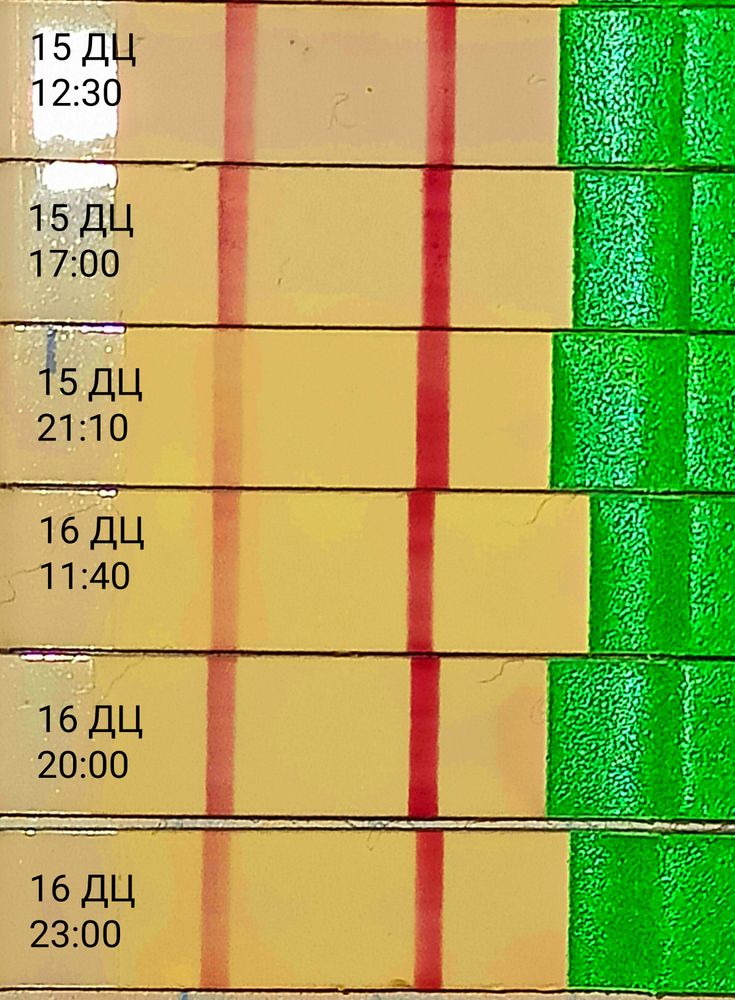

Продолжение...16 ДЦ

Тест снова ярчает вечером сегодня, значит вчера я пик всë таки не пропускала, его просто не было ещё.

Ещё один перед сном замочила и он снова бледнее:

Зачем замочила, до завтра не могла я что ли дотерпеть, сколько тестов уже извела. Достало уже.

Хоть бы завтра уже наступил пик🤞🤞🤞

Ну , хватит уже тупить на одном месте , то ярче то бледнее .

Я думаю не стоит часто мочить тесты на О, они всегда разные в течении дня, всë равно пик сложно пропустить, мочить лучше один раз вечером с 17:00 до 20:00 и в одно и тоже примерно время, а не как я в разноброс.